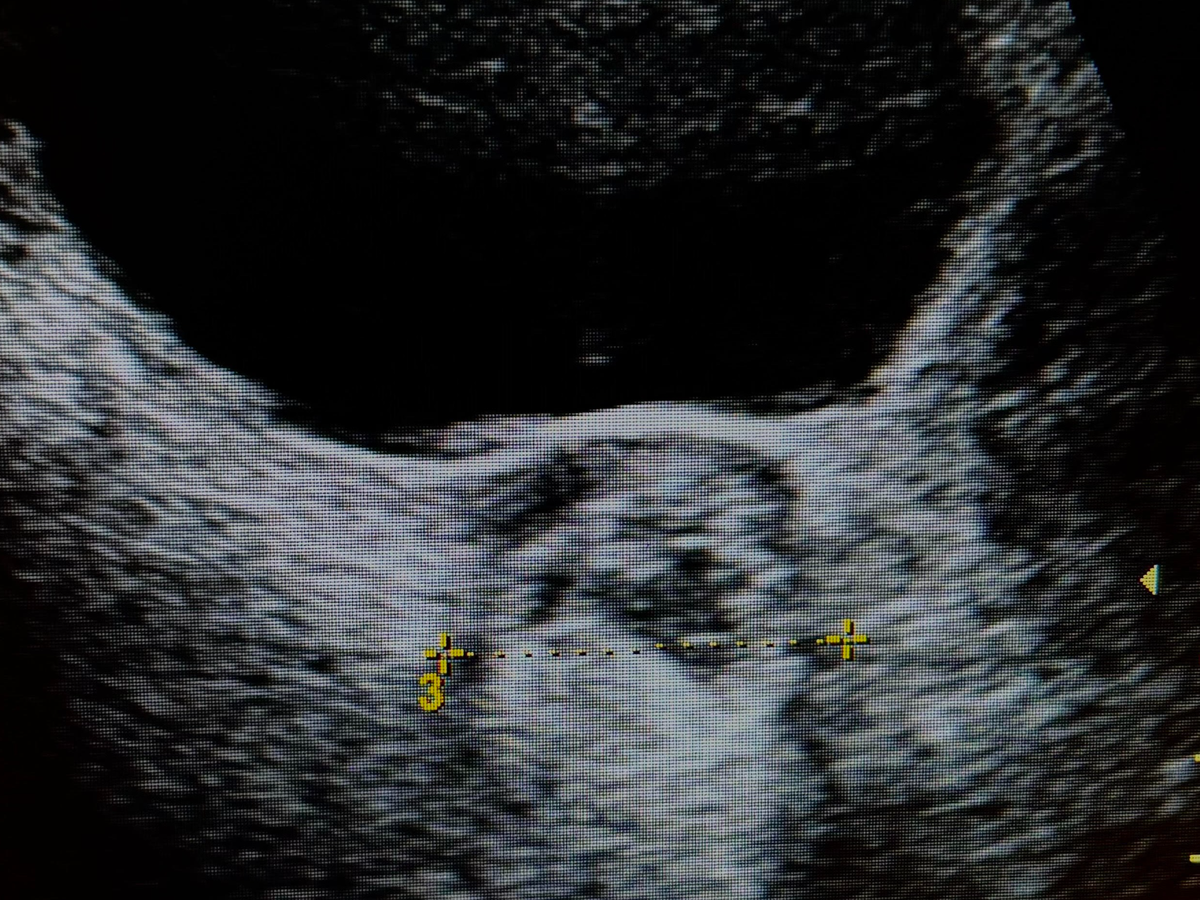

I am in need of a laparoscopic surgery to remove a Dermoid Cyst on my left ovary that I have had since 2024. Normally, most cysts can resolve on their own, but because there is tissue in this cyst, it will not resolve on its own and will only continue to grow. I am at the point of having slight pain/discomfort, and if I do not have surgery to remove it, it will eventually lead to ovarian torsion and can cause me to lose my ovary if left untreated. As someone who hopes to have children someday, it is very important I get this surgically removed sooner rather than later, as it has already been a year and a half of it growing. Even with insurance, I am looking at a high medical bill. Any help towards this surgery is appreciated.